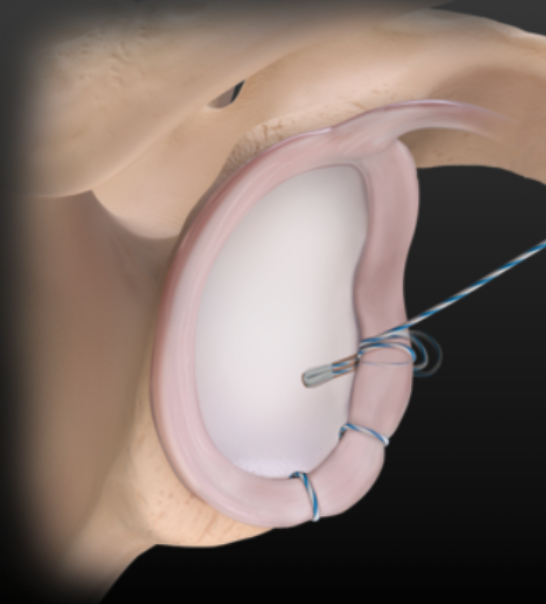

Outcomes of Revision UCL Repair With Internal Brace for Failure of Primary UCL Reconstruction in Professional and Collegiate Baseball Pitchers

Injury of the ulnar collateral ligament (UCL) is common in baseball players. Pitchers are most commonly affected and most likely to have surgery for this injury. The gold standard surgical treatment is UCL reconstruction with autograft; yet, UCL repair with collagen-coated suture tape (ie, internal brace) has shown to be equally effective, and both procedures demonstrate high rates of return to sport and similar postoperative elbow function. However, revision UCL reconstructions have less favorable outcomes regardless of technique.